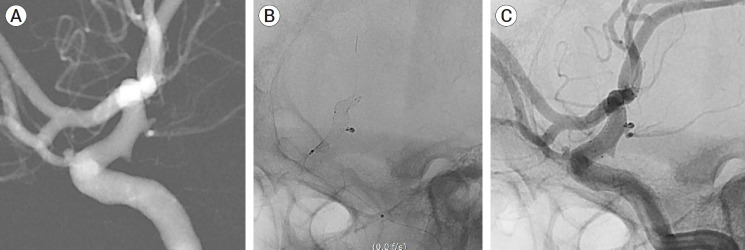

Objective: Stent-assisted coil embolization (SAC) is an effective method of treating intracranial aneurysms. The aim of the study was to assess the safety and efficacy of the new ACCERO stent for the treatment of cerebral aneurysms.

Methods: It was a retrospective, single-center study. Nine ruptured and 41 unruptured cerebral aneurysms were treated using the ACCERO stent between February 2021 and December 2023. Patient demographics, aneurysm characteristics, procedural parameters, grade of occlusion, complications, and clinical outcomes were analyzed. Follow-up was conducted with magnetic resonance angiography (MRA) or Digital subtraction angiography (DSA) was performed 6 to 12 months after the procedure.

Results: The ACCERO stent deployment was attempted in 51 cases, with replacement by the Neuroform Atlas stent in 1 case. Successful stent deployment was achieved in 50 cases, and appropriate wall apposition to the parent artery. The average clinical follow-up period was 17.1 months. Intimal hyperplasia was observed in 1 case, but no other clinical complications related to the stent occurred. Favorable clinical outcomes were observed in 92% of patients (46/50), including those with subarachnoid hemorrhage. Immediate favorable angiographic outcomes and complete occlusion were achieved in 90% (45/50) and 74% (37/50) of cases, respectively. Among the 45 patients who had imaging follow-up, favorable angiographic outcomes and complete occlusion were observed in 93.3% (43/45) and 82.2% (37/45) of cases, respectively.

Conclusions: The ACCERO stent is a braided-type stent that requires more attention than stents, such as the Neuroform Atlas or Enterprise stents. However, since the struts of the stent are fully visible, it can be more useful in treating challenging aneurysms once the user becomes familiar with its use.